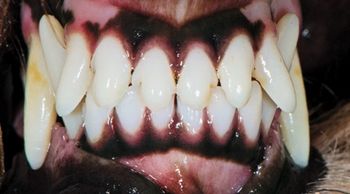

In veterinary medicine, the goal of orthodontic correction isnt a pretty smile but pain-free, functional occlusion.